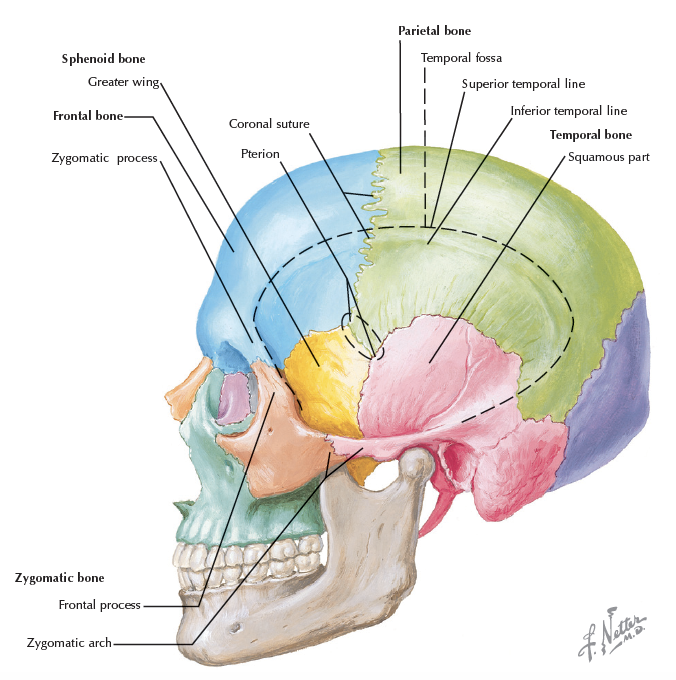

Osteology

骨頭

Parietal bone

- Sagittal suture

- Lambdoidal suture

相鄰骨

F, O, T, S, Pr’

Sphenoid bone

相鄰骨

F, O, T, E, Pr, V, Z, Pl, Mx

Temporal bone

相鄰骨

Pr, O, S, M

Occipital bone

Pr, T, S, C1

Sutures

- Coronal

- Sagittal

- Lambdoidal(人字)

- Squamosal(鱗)

- Temporozygomatic